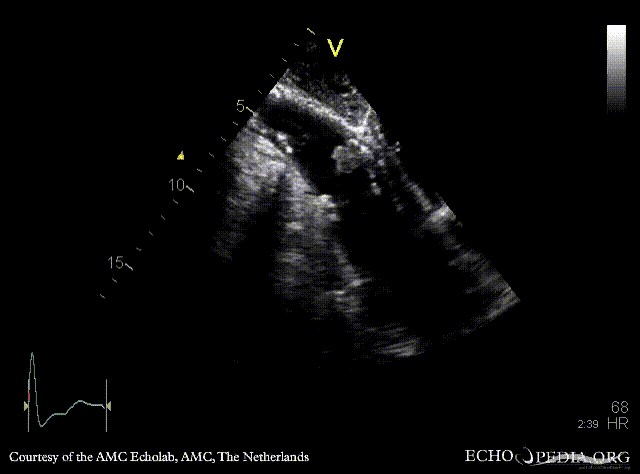

| PLAX: concentric hypertrophy of left ventricle, thickend aortic valve | PSAX: concentric hypertrophy of left ventricle |